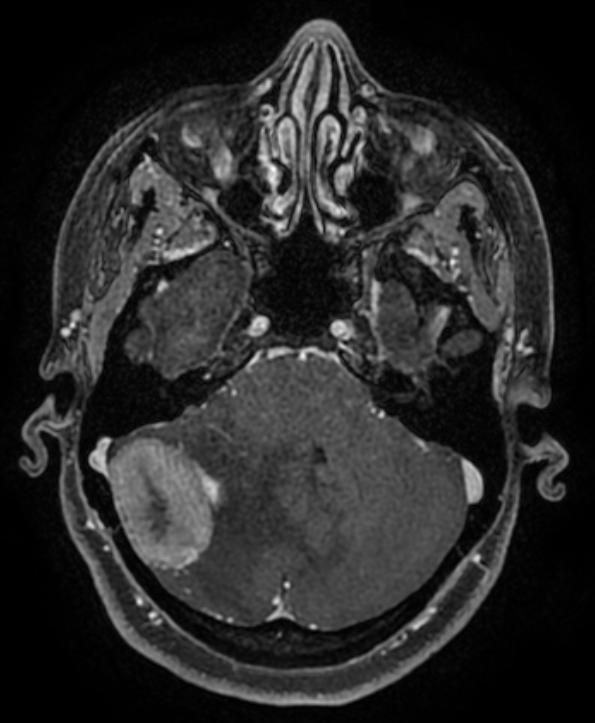

وكانت المريضة تعاني من صداع شديد لا يستجيب للعلاج الدوائي مع وجود غثيان ودوار في الرأس وبعد عمل أشعة الرنين،في مستشفى آخر، تبين وجود ورم في مؤخرة الرأس بحجم ٣x٣.٥ سم مع وجود استسقاء دماغي حاد نتيجة انسداد مجرى تصريف السائل النخاعي، وتم قبول الحالة بعد التواصل مع قسم جراحة المخ والأعصاب وعند وصول المريضة تم عمل أشعة الرنين بالصبغة في نفس اليوم بالتنسيق مع أطباء الأشعة المناوبين د.ريم الأمير و د.آيات الدرويش.